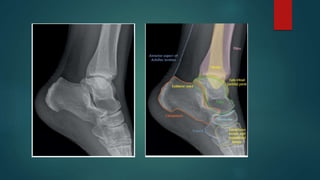

Skeletal X ray anatomy ,colour description, Imaging anatomy of musculoskeletal X rays, Diagnosis imaging anatomay, Radiology